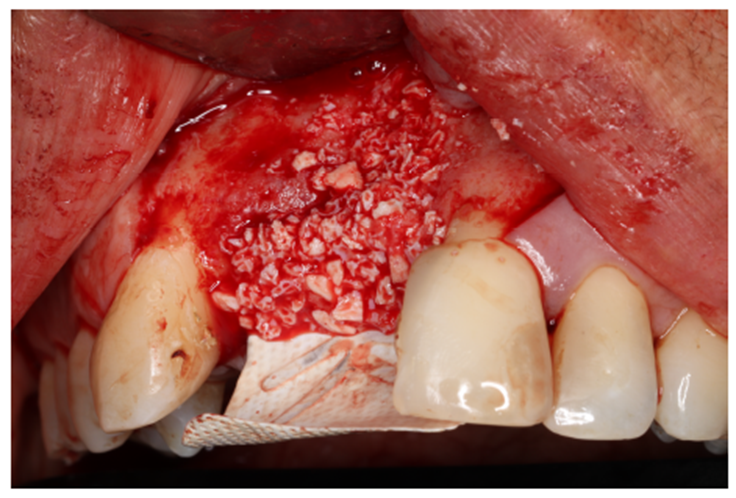

O material de enxerto ósseo particulado (Bio-Oss) foi preparado junto com as membranas de fibrina autógenas (L-PRF). O mesmo foi levado e acomodado no arcabouço entre as membranas e o osso descorticalizado. É de suma importância que toda a região que, posteriormente, receberá um implante dentário seja totalmente recoberta pelo material de enxerto e as membranas de PTFE-d, para que não ocorram GAPS que impossibilitariam uma futura reabilitação. (Figuras 6.1 e 7.1).